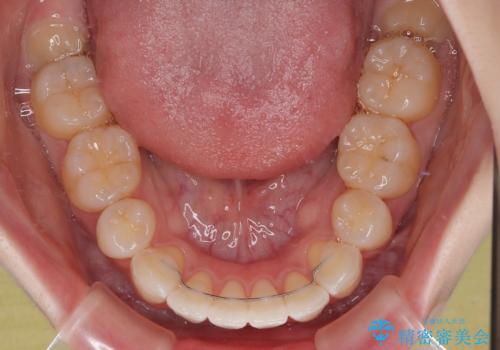

舌の突出癖により、口元が突出しているだけでなく、上下前歯が非接触となっておりました。

舌のトレーニングをしっかりと行っていただくことで、2年を切って治療を終えるとともに

、上下前歯を接触させることができました。